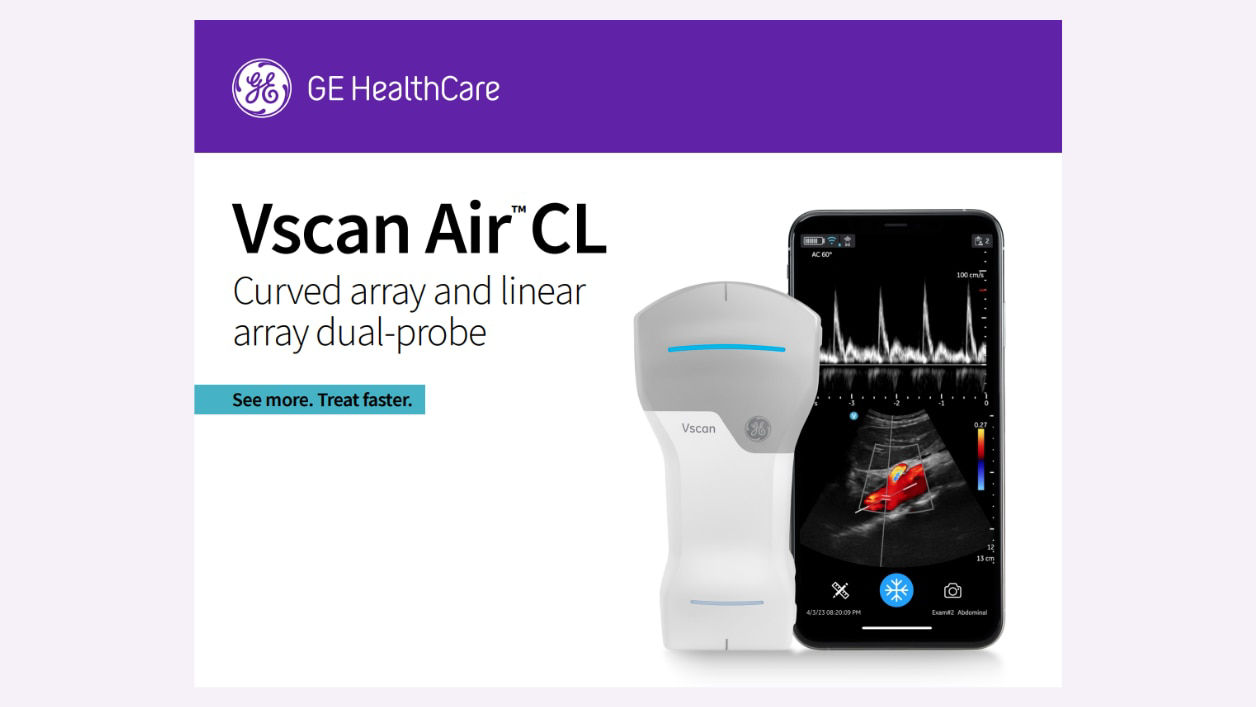

Cost effective

Vscan Air provides a cost effective ultrasound solution for your primary care practice.

AI supported

Available AI features assist in clinical image interpretation and can help enhance diagnostic accuracy.

Enhanced patient care

Vscan Air enables early detection of various conditions, allowing for timely interventions and improved prognosis.

Easy to use

Seamless pairing with a mobile device and intuitive to navigate.